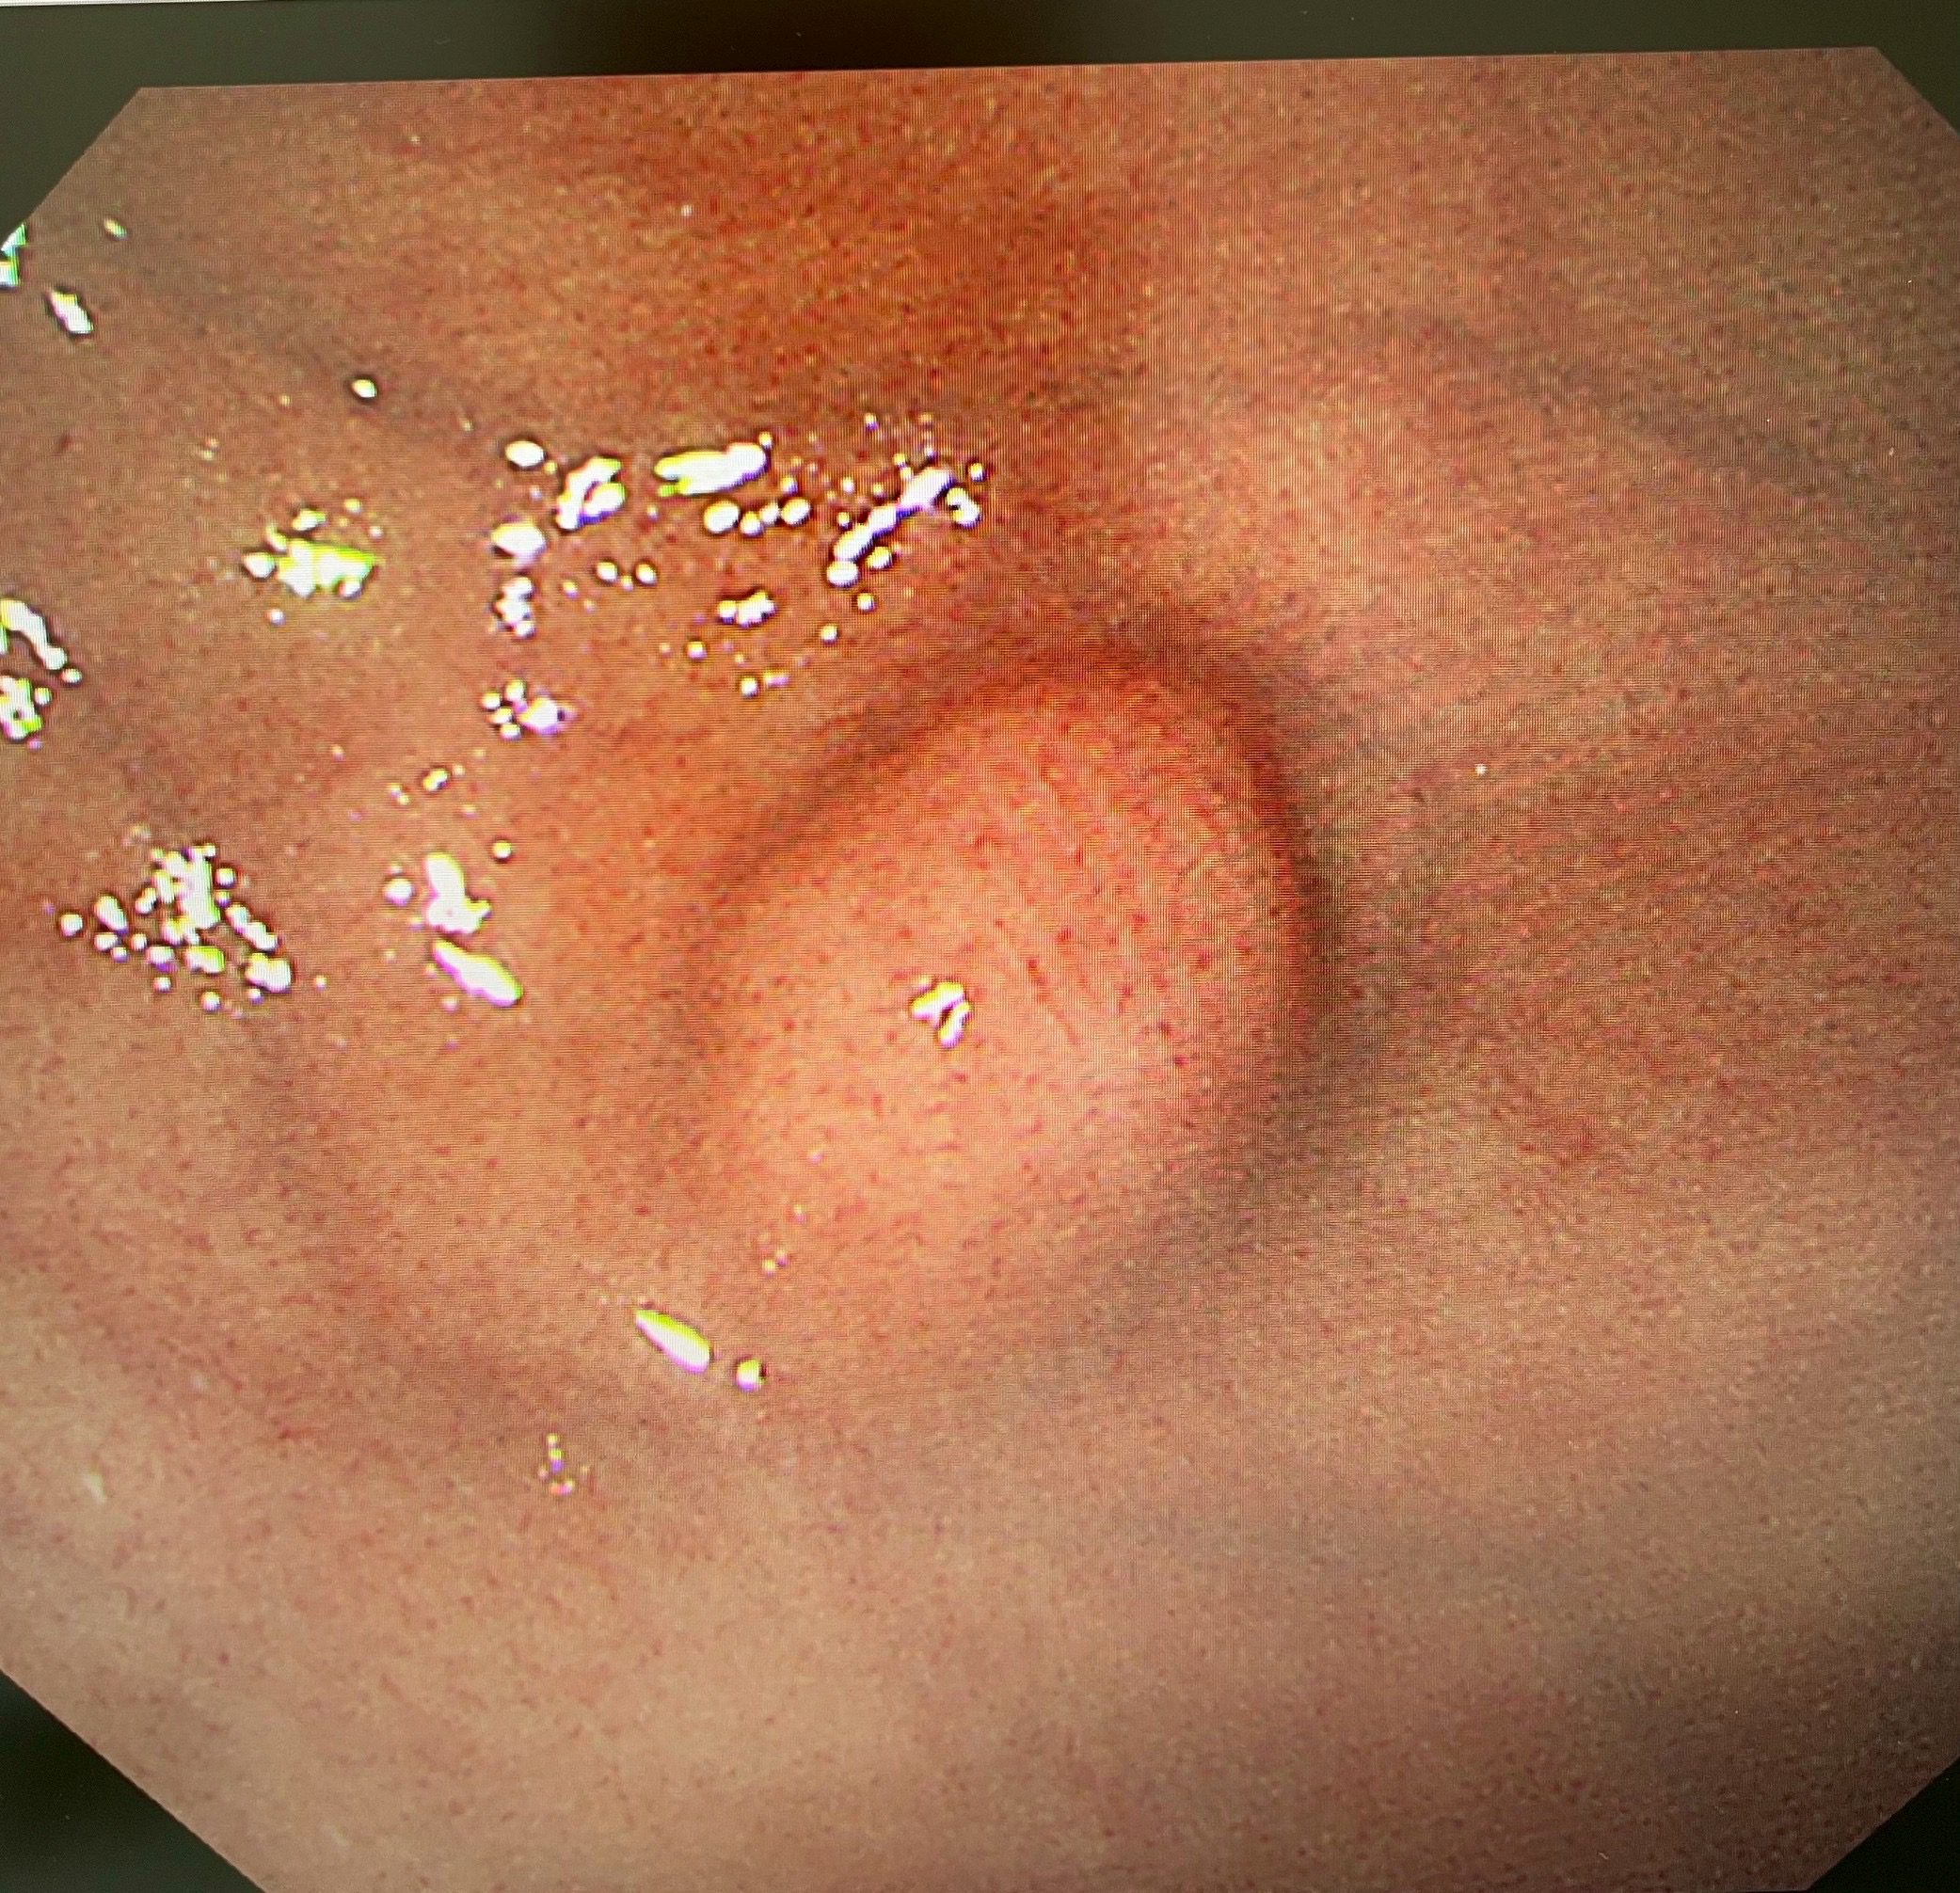

一位59歲單身女性多年前檢查發現胃部有一黏膜下腫瘤,雖被醫師告知需定期追蹤,卻因無不適症狀而未多加留意。直到今年8月回院複查,發現腫瘤已成長至1.3公分,位於胃上半部,經詳細檢查高度懷疑為「胃間質瘤」(GIST),2公分以下間質瘤雖然風險度極低然病患經深思熟慮後,認為後續的追蹤及要面對未來可能癌變的風險,對其心理層面造成極大的壓力,毅然決定選擇內視鏡手術切除。幸運的是,在新型內視鏡手術技術的幫助下,醫師僅花25分鐘就成功完整切除腫瘤(R0),患者術後12小時即可進食,第二天便出院返家,創下胃部腫瘤治療新里程碑。

該患者轉至陳鴻運醫師門診後,醫療團隊為她安排了上消化道內視鏡、內視鏡超音波(EUS)及電腦斷層檢查。內視鏡超音波檢查顯示,腫瘤已生長至胃壁第四層(固有肌層),但幸運的是沒有附近淋巴結及遠處轉移的跡象。

「內視鏡超音波是評估黏膜下腫瘤的黃金標準工具」,陳鴻運醫師說明:「它能清晰顯示胃壁的五層結構,準確判斷腫瘤的起源層次、大小和特性,幫助我們制定最合適的手術方案。」